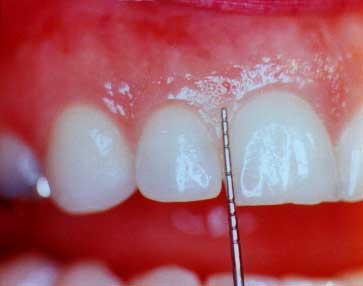

periodontal probe

The Periodontal Probe

This print shows the probe outside of the gum "sulcus" in order to show just how deep it would have gone (2-3 mm) in this healthy "sulcus"

Please remember from 2. The Cause of Gum Disease, when the gums are infected, they detach from the teeth and form the probing depths that are deeper than 3 millimeters. The following case types will show probing being done and you will see the silver periodontal probbe. Healthy gums look healthy and probing into the "ditch" or "sulcus" only goes to a depth of 1-3 millimeters. Disease gums show changes in color, form and texture, and also show a probing depth deeper than 3 millimeters.